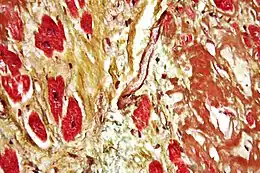

Fibrose musculaire

Lors de lésion profonde sur les muscles striés (destruction de la membrane basale et myoblaste) alors la régénération se fait à partir des tissus conjonctifs ce qui conduit à une fibrose.